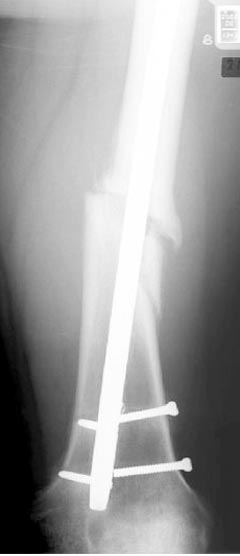

Из трех вариантов:

Рассверливание с заменой более большого диаметра штифтом,

Остеотомия с фиксацией пластиной+костная пластика,

Аппарат Илизарова= Taylor spatial frame

Гвоздь для ротационных смещениц был бы идеальнымимплантом, после коррекции есть возможность блокировать, но из-за укорочения метод оставил на последнее место. Есть метод Сhaplan лечения ложных суставов бедра, где необходимость bone graft, накладывается феморальный дистрактор и после удаления штифта - рассверливание, через проксимальный канал вводят костный графт в место ложного сустава под рентген контролем, потом вводят штифт, кстати, само рассверливание дейстивует как стимулятор - активизирует восстановительный процесс.

Обычный мой первый выбор - вариант с пластиной, - учитывая бывшую инфекцию, открытую травму, посчитал метод менее приемливым.

Еще больной был противв костной аутопластики, да и самому тоже хотелось перейти к истокам "откуда мы" более усовершенствованному Курганскому методу.

Операцию провели в два этапа, сперва удалили штифт, рассверливание римером на пару мм большего диаметра, определение чувствительности на анаэробную и аэробную культуру (где исследования показали негативный результат чувствительности), через дней десять - начали аппаратную фиксацию.